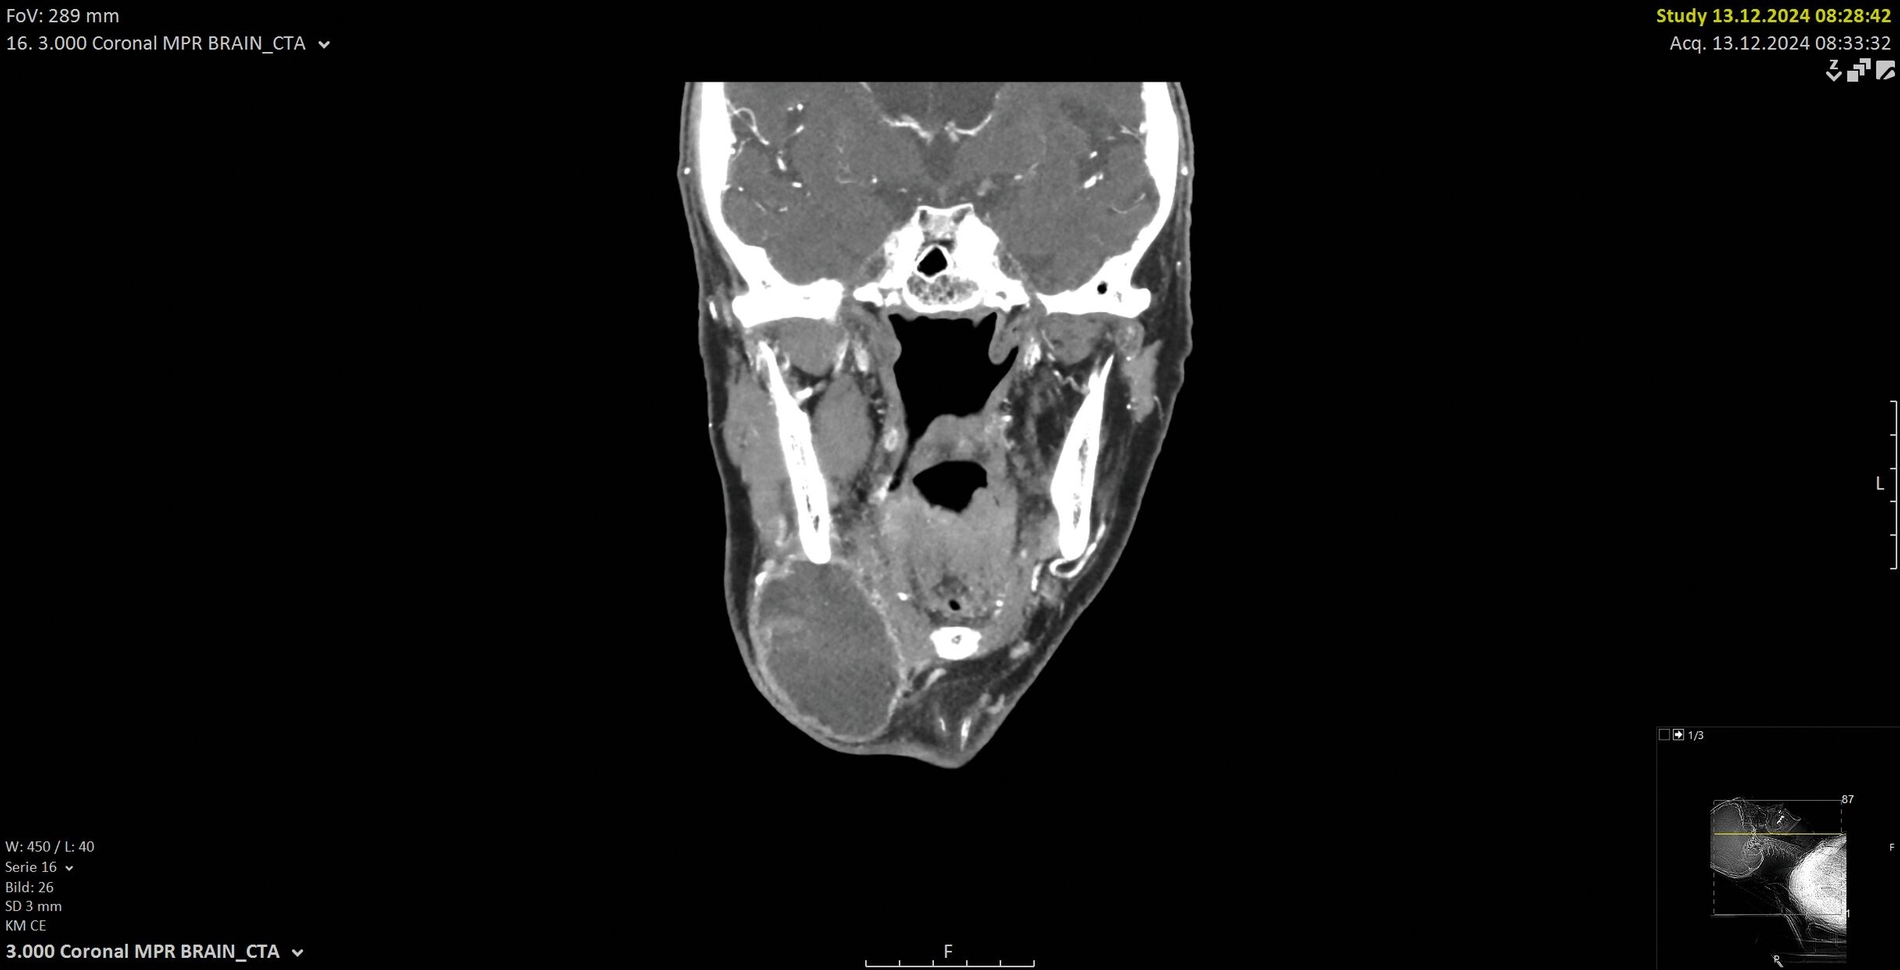

Eine kontrastmittelgestützte Computertomografie (CT) zeigte eine 6 cm x 5 cm x 4 cm große Raumforderung submandibulär rechts mit inhomogener Kontrastmittelaufnahme und teils zystischer Binnenstruktur (Abbildung 1). Der Befund wies morphologisch auf eine maligne Genese hin. Ein weiterführendes Staging mittels CT-Thorax und Abdomen zeigte keine Anzeichen für Fernmetastasen oder weitergehende Lymphknotenmanifestationen. Dem Patienten wurde die Indikation zur operativen Entfernung der Raumforderung im Sinne einer erweiterten Exzisionsbiopsie erläutert. Es wurde mit ihm besprochen, dass bei intraoperativem Nachweis eines malignen Befunds eine onkologische Resektion mit Sicherheitsabstand sowie eine elektive Neck Dissection der Level II–IV erfolgen würde. Ebenso wurden verschiedene Rekonstruktionsmöglichkeiten für den Fall eines größeren Defekts erörtert.

Nach submandibulärer Freilegung der inhomogenen Raumforderung wurden multiple Proben entnommen. Im Verlauf der Exzision entleerte sich eine hornartige Substanz (Abbildung 2). Die intraoperative Schnellschnittuntersuchung ergab in sämtlichen Proben die Manifestation eines mäßig differenzierten, verhornten Plattenepithelkarzinoms mit ausgeprägter chronisch-resorptivzelliger Entzündung und Fremdkörperreaktion. Daher erfolgte die Resektion der Raumforderung mit adäquatem Sicherheitsabstand unter Mitnahme der adhärent wachsenden Hautanteile in toto (Abbildung 3). Zusätzlich wurde eine selektive Neck Dissection der Level II–IV durchgeführt. Der entstandene Defekt wurde unter Berücksichtigung der funktionellen und ästhetischen Aspekte mittels eines freien, mikrovaskulär anastomosierten anterolateralen Oberschenkellappens (ALT-Lappen) rekonstruiert (Abbildung 4).

Die endgültige histopathologische Analyse bestätigte die Diagnose eines mäßig differenzierten, zystisch umgewandelten Plattenepithelkarzinoms mit einer Tumorgröße von 5,8 cm. Es zeigte eine Infiltration des umgebenden Weichgewebes und der Epidermis, aber keine perineurale Invasion, während perifokal erhaltenes Speicheldrüsen-Parenchym nachweisbar war. Eine vollständige Resektion mit freien Resektionsrändern (R0-Resektion) wurde pathologisch bestätigt. Alle 23 entnommenen Lymphknoten waren tumorfrei.